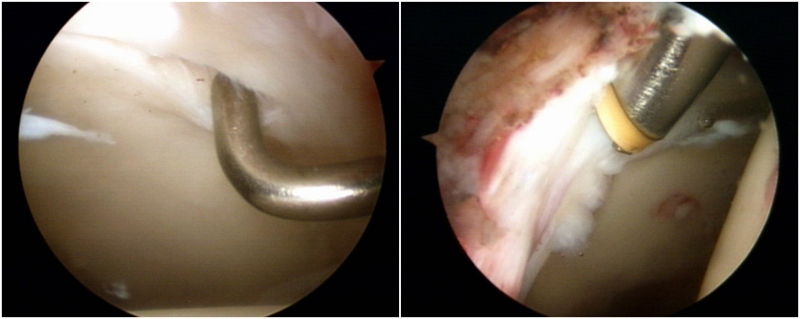

图8 术中

手术方式的选择上目前主流上均通过髋关节镜微创手术进行治疗。通过2-4个长度约0.5cm长的手术切口即可完成全部手术过程。

1.解决骨性异常问题:作为引起髋关节撞击综合征的主要原因,解决髋臼和头颈结合区的异常骨性凸起是髋关节镜的重要步骤。在关节镜下,将异常凸出的骨质磨削。手术解决pincer或cam畸形,通常是一件“一劳永逸”的工作,将髋关节的骨性结构成型后,髋关节的撞击症状也随之解除,而pincer和cam畸形通常情况下不会复发。

图9 Cam型撞击,通过磨钻磨除

2.盂唇损伤的治疗:盂唇损伤广泛存在于髋关节撞击综合征中。对于存在修复条件的盂唇损伤,目前推荐行盂唇修复术;而对于盂唇严重磨损无法修复或横断的情况,则可考虑行盂唇清理、盂唇部分修复或盂唇重建术。手术原则是对损伤的髋臼盂唇尽量予以缝合修复,恢复髋臼盂唇的解剖结构,从而恢复髋臼盂唇的功能,避免由于髋臼盂唇缺损造成的髋关节退变。

图10 髋关节盂唇损伤及修复